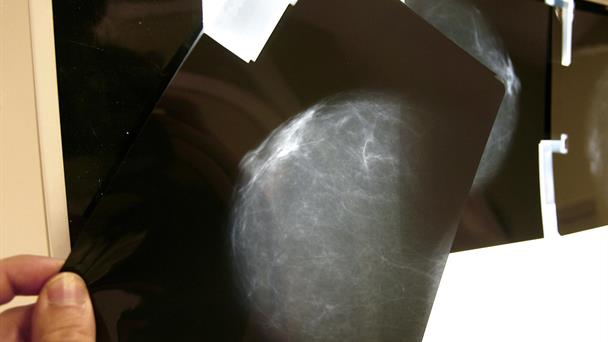

Un estudio del Instituto de Salud Carlos III de España, basado en el análisis de 714 pacientes con cáncer de mama, sugiere que tener mayor densidad mamográfica podría estar relacionado con el desarrollo de algunos tumores, como los HER2+ o los triple negativo, que son los más agresivos y con peor pronóstico.

La densidad mamográfica mide la proporción de tejido fibroglandular de una mama, frente a la cantidad de tejido graso. Cuanto más densas, más tejido fibroso tienen y mayor es el riesgo de cáncer de mama.

El 69% de las participantes presentó tumores HR+, un 19% el subtipo HER2+ y un 12% el triple negativo, y la densidad mamográfica media fue del 26%.

Las mujeres con densidad mamográfica superior al 50% presentaron un menor porcentaje de tumores con mejor pronóstico (HR+), mientras que el porcentaje de tumores HER2+ y triple negativo -los más agresivos- fue un 36% y un 23% mayor, respectivamente, en comparación con las mujeres del grupo de menor densidad.